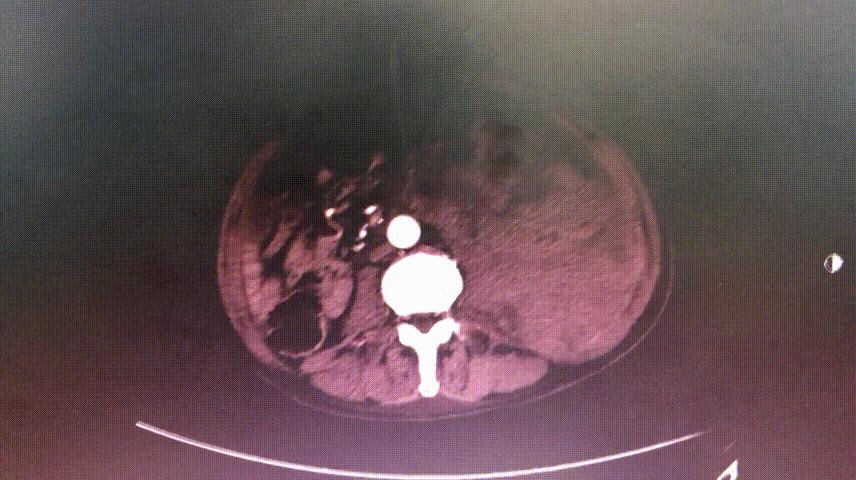

术后行急诊CT检查

TAVR术后3日Hb较前下降 (63g/L)

CT提示左侧腹膜后、髂窝及腹股沟区巨大血肿